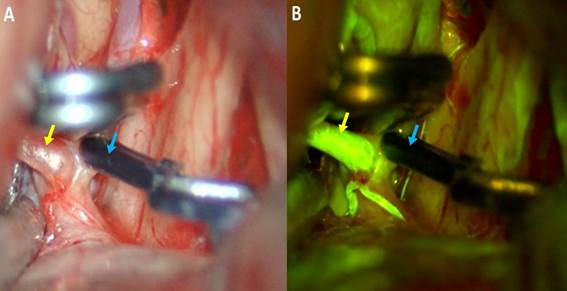

El paciente en posición supina con la cabeza por encima del nivel cardiaco, lateralizada 15 grados. Se realizó un afeitado mínimo de la zona, luego se procedió a una incisión cutánea de 6cm. El colgajo piel-galea se desplazó hacia anterior. El musculo temporal se disecó en su porción antero superior. Craneotomía de 3 x 4 cm, mucho más pequeña que un pterional clásico. Drilado del ala esfenoidal desde la pared orbitaria hacia el ala menor esfenoidal. Apertura de la duramadre en C hacia frontal. Bajo visión por microscopia se inició la disección intradural, llegando a las cisternas basales para liberar líquido cefalorraquídeo y relajar el cerebro, posteriormente se ubicó el aneurisma cerebral (Figura 3). “Clipaje” total del aneurisma con control de angiografía con fluoresceína (Figura 4), observando la patencia vascular de arterias madre y perforantes. Control de hemostasia, cierre dural luego por planos hasta piel.

Figura 4 A: Imagen intraoperatoria, que muestra la oclusión completa del aneurisma (flecha azul). B: Angiografía con fluoresceína intraoperatoria que muestra la permeabilidad del entrono vascular (flecha amarilla).

En el control postoperatorio se observó una oclusión total del aneurisma y permeabilidad de ambas arterias cerebrales anteriores de los segmentos A1 y A2. El paciente tuvo evolución favorable con estancia hospitalaria corta (Figura 5).